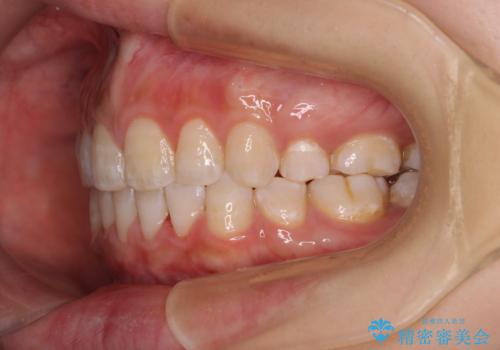

前に出ている上顎 抜歯矯正で唇を閉じやすく

第二小臼歯抜歯はイレギュラーな治療手段であり、治療期間が延びる傾向にありますが、舌のトレーニングをしっかりと行ってくださり、2年弱という非常に短い期間で理想的な仕上がりを達成することができました。

- 口元の突出感と上下前歯のズレを気にして来院された患者様です。

舌の突出癖により上下の前歯は非接触であり、更には奥歯の咬み合わせが非対称となっている状態でした。